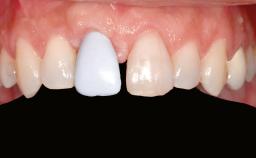

A woman in her mid-fifties was referred by a dental student for dental implant placement. Both posterior segments of the mandible had been edentulous for more than 4 years, the only residual tooth being the right lower first premolar. The patient had used a removable partial denture but was not entirely satisfied with its function. The clinical examination revealed a sharp edentulous ridge in both posterior segments of the mandible, and the patient was told that it would not be possible to insert implants into this thin edentulous ridge without significant augmentation of the alveolar ridge. Her medical history revealed no significant findings and no underlying disease that might have complicated surgical procedures. During the presurgical examination, the patient reported that she was a little apprehensive about bone grafting. After being informed about the surgical procedures and potential postoperative complications, she accepted the proposed surgical plan of bone grafting and subsequent placement of implants.

| Prosthesis Type | FDP |